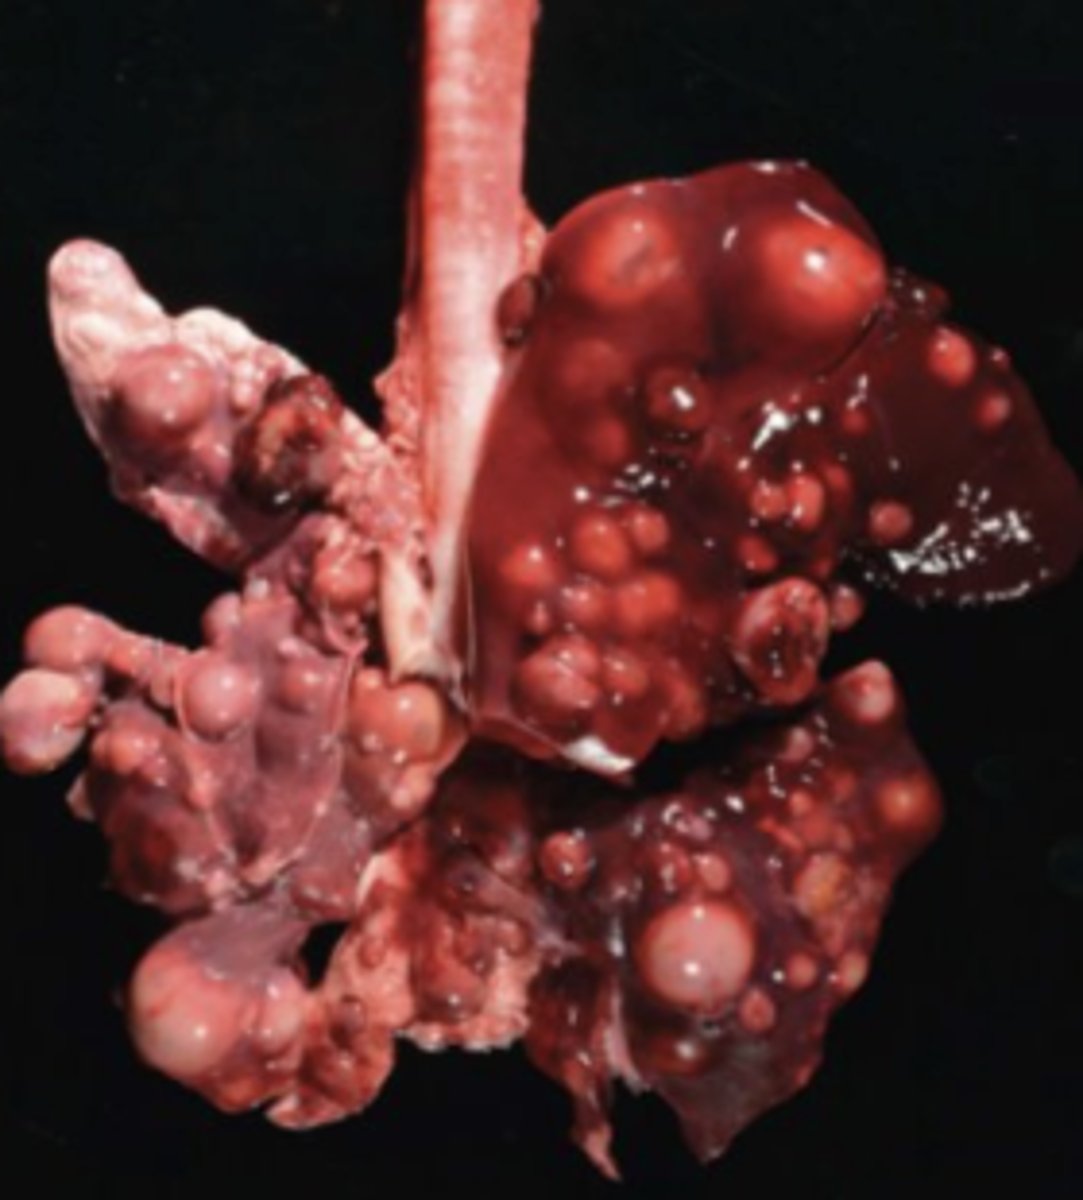

BLV Lymphoma

-nodular

What has caused this gross appearance of this bovine liver?